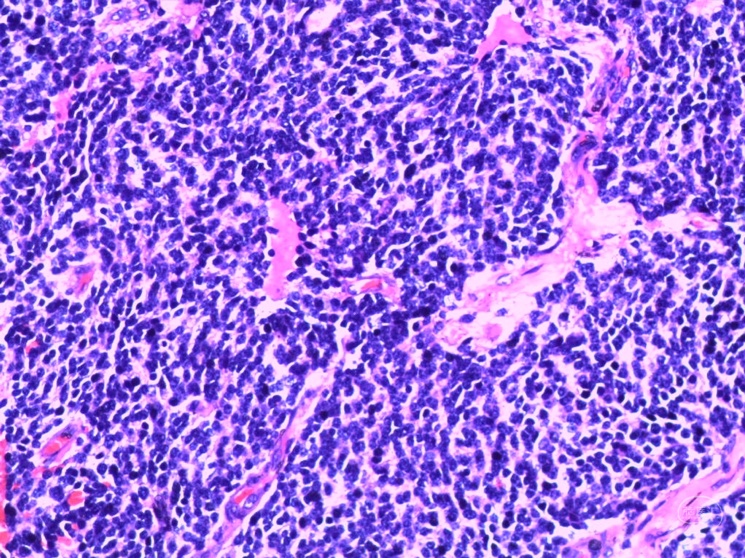

本次术前CT

诊断:右侧蝶窦外侧隐窝脑膜脑膨出伴脑脊液漏。

病因分析:患者蝶窦过度气化,一直延伸至翼突,形成蝶窦外侧隐窝,造成中颅窝底出现薄弱区。患者第一次手术前因为松果体肿瘤,造成严重脑积水,颅内压明显增高,促使脑膜脑组织自颅底薄弱区疝出。但第一次手术术前并无脑脊液漏,而术后才出现脑脊液漏,可能的原因是:术前脑积水,造成颅内压较高,增高的颅内压一方面促使脑膜脑膨出,另一方面也迫使脑组织堵塞住了漏口,因而未出现脑脊液漏,手术后肿瘤全切除,脑积水缓解,颅内压下降,使得脑组织的堵塞漏口的作用下降,因此反而出现了脑脊液漏。